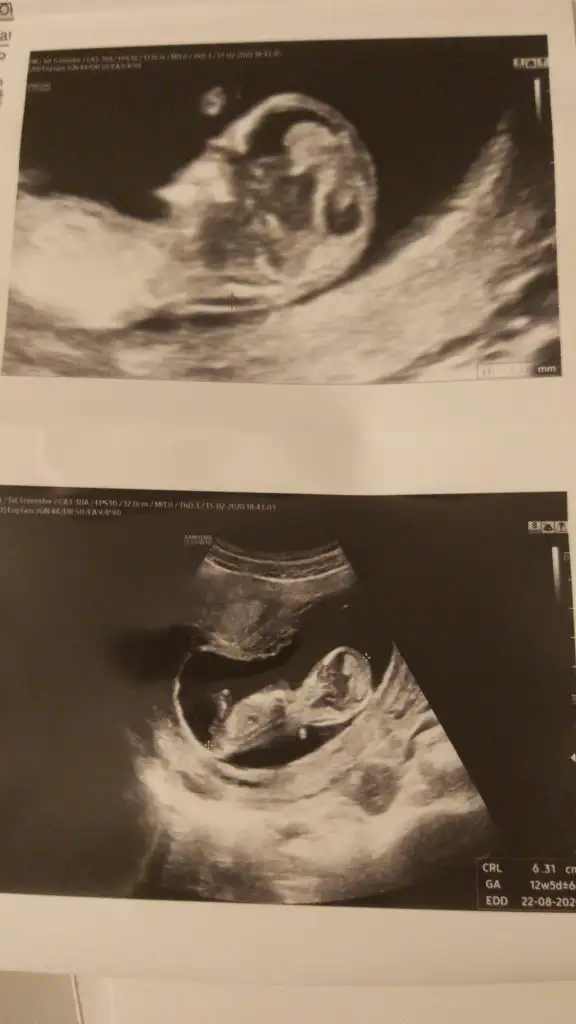

dr soylemeden siz gorun genital nub teorisi ( bebegin cinsiyeti)

Banada tahmin yaparmısınız hanımlar 12+5 günlük .